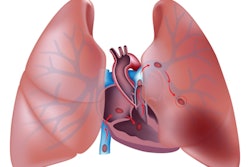

Artificial intelligence (AI) software developers Aidoc and Imbio have formed a partnership to develop an AI package for the detection and quantification of pulmonary embolism (PE).

Designed to assist thoracic radiologists, the combined offering is currently available for investigational use only.